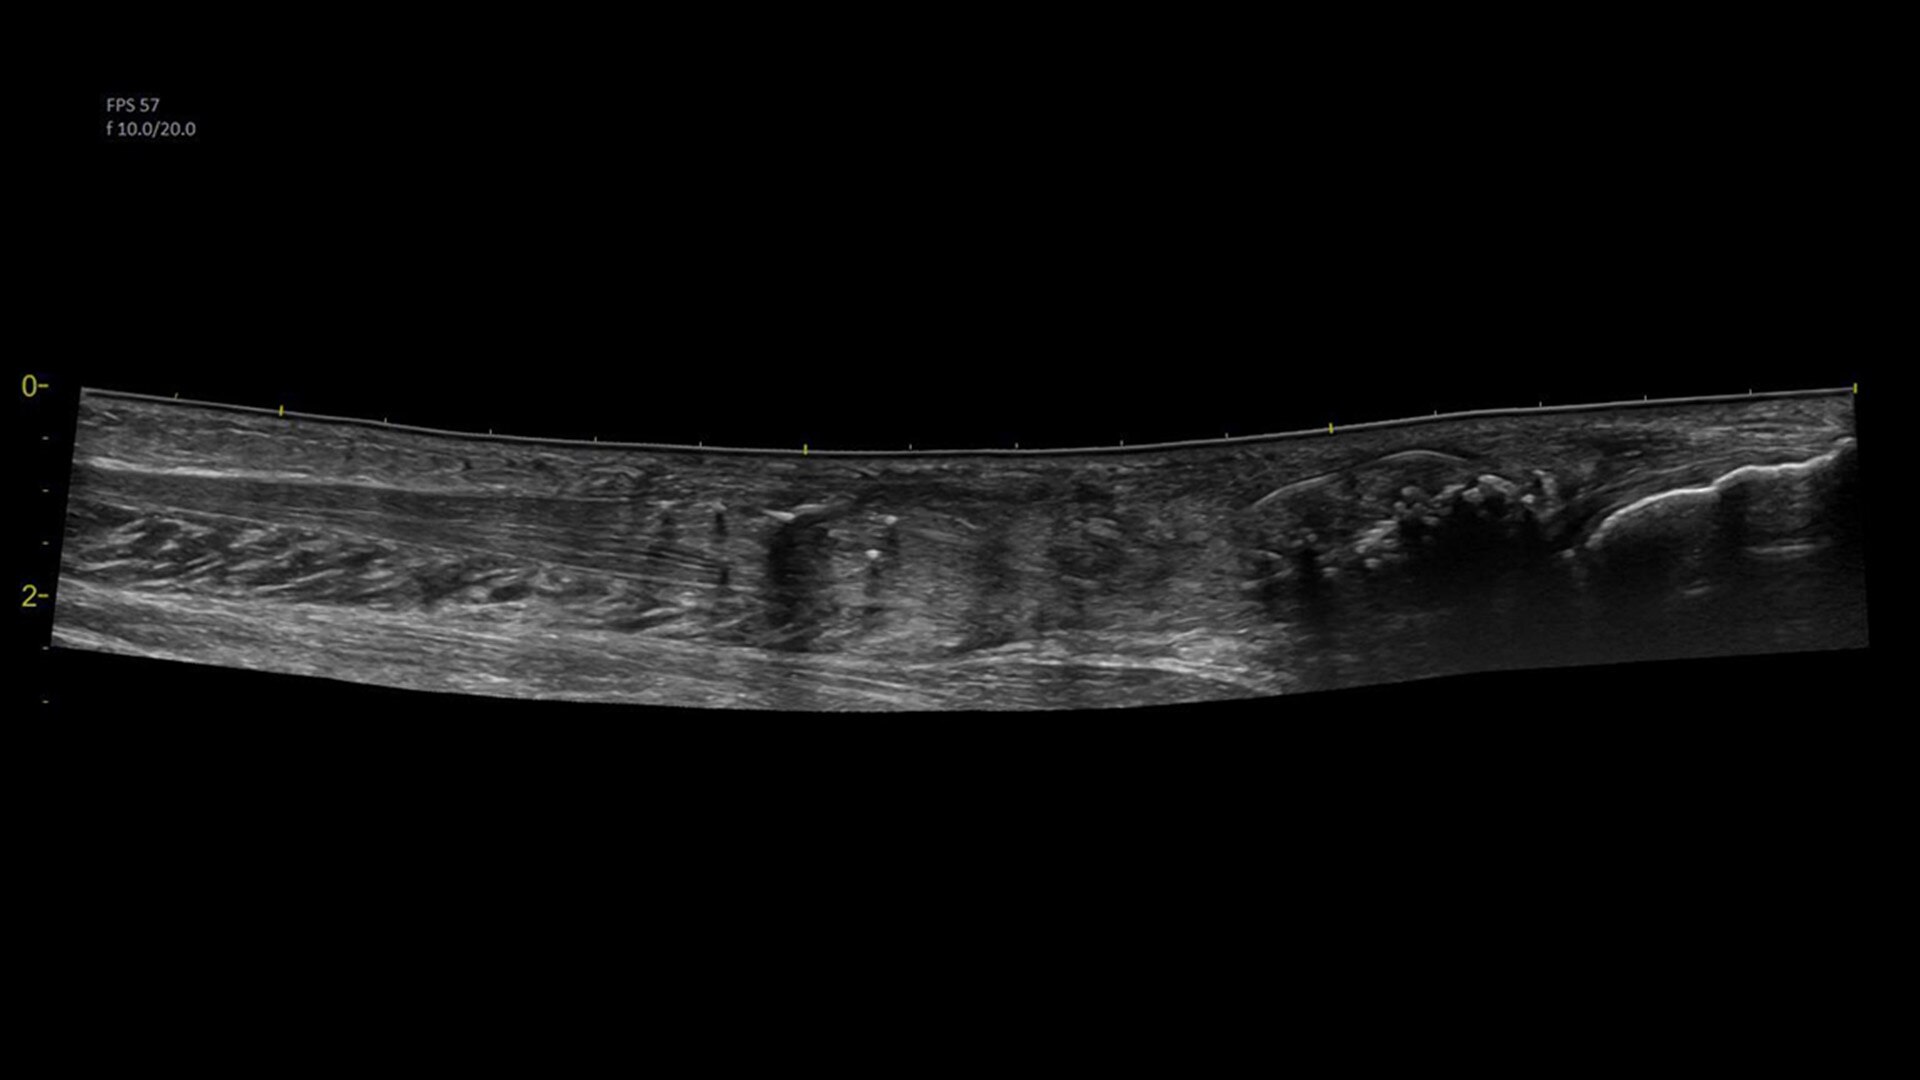

Visualize more anatomy in a single scan with Virtual Convex

This tool provides a wide field of view so users can visualize more large anatomy structures in a single scan.

Easily see the anatomy you need to see with Venue View

Supporting diagnostic confidence by constructing a panoramic image from individual frames, Venue View allows you to view up to 60cm of anatomy being scanned with anatomical relationships in one view.1